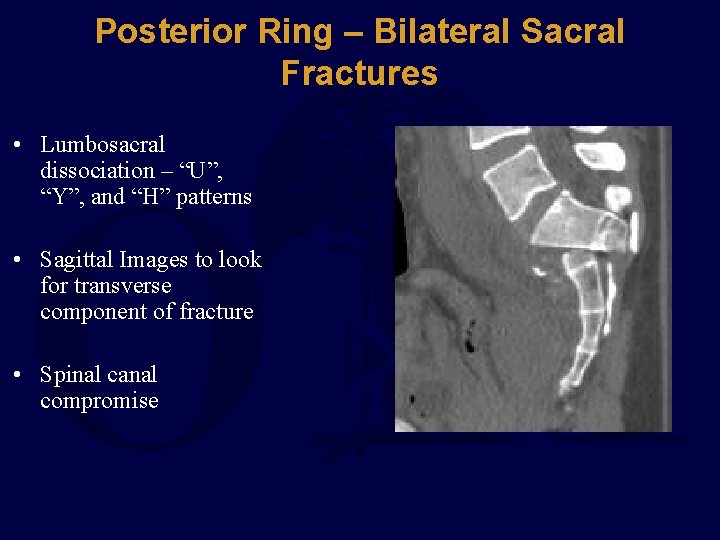

Posterior Ring – Bilateral Sacral Fractures • Lumbosacral dissociation – “U”, “Y”, and “H” patterns • Sagittal Images to look for transverse component of fracture • Spinal canal compromise